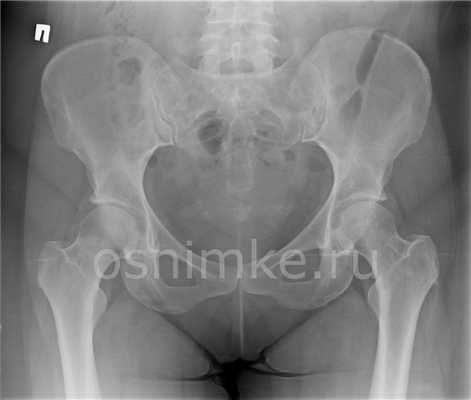

В начальных стадиях (1-2 стадии по Kellgren) ОА тазобедренных суставов при рентгенологическом исследовании определяются: незначительное сужение суставной щели, слабовыраженный субхондральный остеосклероз, точечные кальцификаты в области наружного края крыши вертлужной впадины (зачаток остеофитов), заострение краев ямки бедренной головки в области прикрепления круглой связки бедренной головки (рис. 1).

При вторичном диспластичном коксартрозе все рентгенологические симптомы развиваются рано (в молодом или среднем возрасте) и могут закончиться асептическим некрозом бедренной головки и подвывихом или полным вывихом бедра.

Описан ишемический коксартроз с быстрым сужением суставной щели, перестройкой костной структуры в головке и шейке бедренной кости, ранними остеосклеротическими изменениями, но без значительного остеофитоза, с достаточно быстрым развитием деструкции бедренной головки.

На рентгене признаки вывиха или дисплазии тазобедренных суставов визуализируются в виде вертикального и бокового смещений головки бедренной кости от вертлужной впадины тазовой кости (измеряемого на полученном снимке и сопоставляемого с анатомической нормой). Поверхность головки бедра часто не соответствует вертлужной впадине тазовой кости, например, при большом размере головки и недостаточной глубине впадины. А угол наклона плоскости входа в нее превышает норму.

Также отмечаются смещение центра вертлужной впадины, уменьшение или увеличение шеечно-диафизарного угла (определяемого между вертикальными осями шейки бедренной кости и ее телом — диафизом).

Еще один немаловажный рентген признак данной патологии — излишний наклон вперед узкой части бедренной кости (шейка бедра), который рентгенологи называют преувеличенной антеторсией.